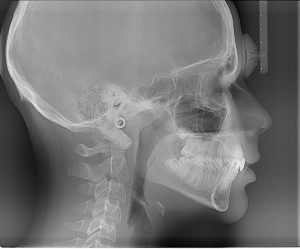

What is fluoroscopy?

through the part of the body being examined. A continuous X-ray beam is passed through the body part and transmitted to a video monitor so that the body part and its motion can be seen in detail. Fluoroscopy, as an imaging tool, allows doctors to look at many body systems, including the skeletal, digestive, urinary, respiratory, and reproductive systems. Fluoroscopy may be used to evaluate specific areas of the body, including the bones, muscles, and joints, as well as solid organs, such as the heart, lung, or kidneys.

through the part of the body being examined. A continuous X-ray beam is passed through the body part and transmitted to a video monitor so that the body part and its motion can be seen in detail. Fluoroscopy, as an imaging tool, allows doctors to look at many body systems, including the skeletal, digestive, urinary, respiratory, and reproductive systems. Fluoroscopy may be used to evaluate specific areas of the body, including the bones, muscles, and joints, as well as solid organs, such as the heart, lung, or kidneys.Fluoroscopy is used in many types of exams and procedures including:

What does a chest x-ray show

Chest X-rays are used to determine the cause of symptoms such as chest pain, trouble breathing, persistent coughing and coughing up blood, reports MedlinePlus. They are also used to diagnose or rule out conditions such as lung disease and tuberculosis. There are many causes of an abnormal chest X-ray. A physician is able to diagnose pneumonia, lung tumours, collapsed the lung, scarring of the lung tissue and other respiratory problems using this test. If the heart is an abnormal size or shape, a physician is able to see the abnormality on a chest film. Chest X-rays also show problems with the position and shape of the large arteries. Because the ribs and spine are visible on a chest film, this type of X-ray is also used to diagnose osteoporosis, rib fractures and spine fractures.

Chest X-rays use a small amount of radiation. In fact, a person receives a similar amount of radiation from a chest X-ray as he would from 10 days of natural radiation exposure.

X-ray machines are designed to permeate the surfaces of lighter objects and materials, such as skin and soft tissues. While beams pass easily through these body parts, they are not absorbed by denser materials, such as bone. The reflection of X-ray beams from dense objects appears as light areas on X-ray films, which identify bone structures and illuminate the skeleton.

This process starts with the generation of electricity, which happens when the machine is turned on. Electrical energy is then carried through a compressed X-ray tube, which transforms energy into multiple X-ray beams. These beams are highly concentrated and exist in various levels of energy. Beams with low energy are blocked, while high-energy beams pass through dense surfaces to provide technicians with a clear image of the skeleton.